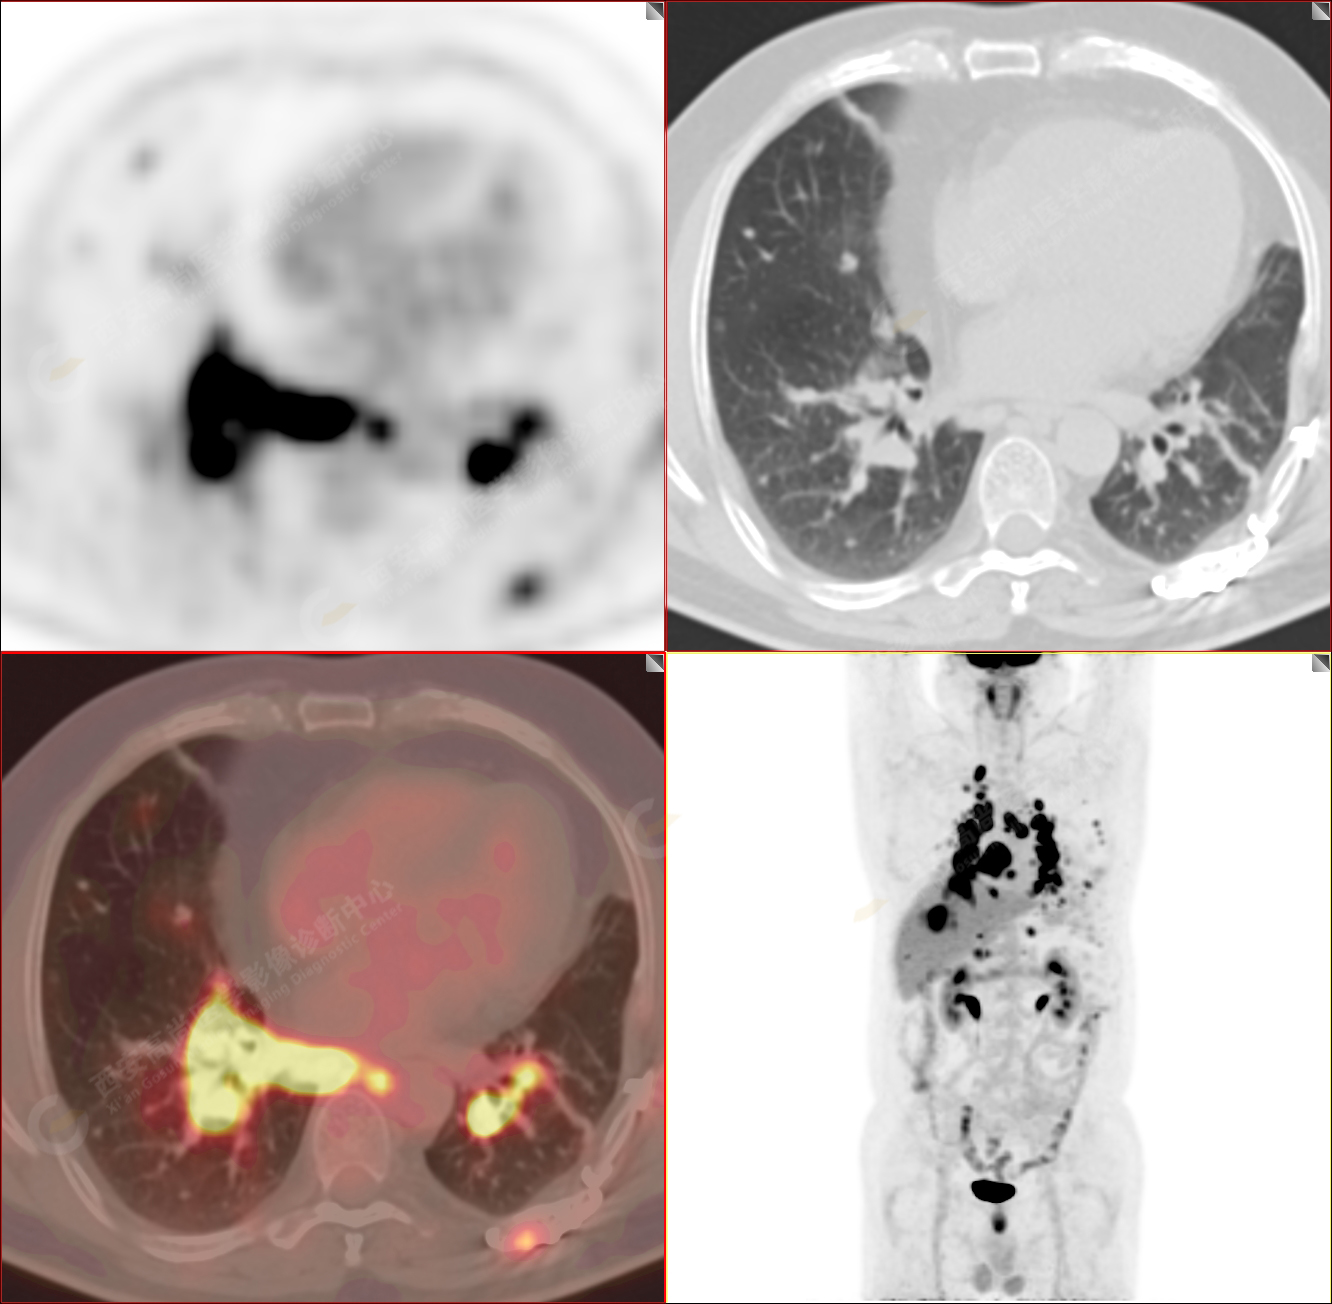

PET/CT-MR診斷結(jié)節(jié)病雙肺及全身多發(fā)淋巴結(jié)廣泛累及1例【西安高尚病例】

男性,53歲,頭暈半月入院,CT發(fā)現(xiàn)肺內(nèi)腫塊,雙肺多發(fā)大小不等實(shí)性及粟粒樣結(jié)節(jié),雙肺門(mén)及縱隔多發(fā)腫大淋巴結(jié)。病程中無(wú)發(fā)熱、胸悶氣及胸部不適。既往:左側(cè)肋骨外傷史。

PET/CT圖像

PET-MR圖像